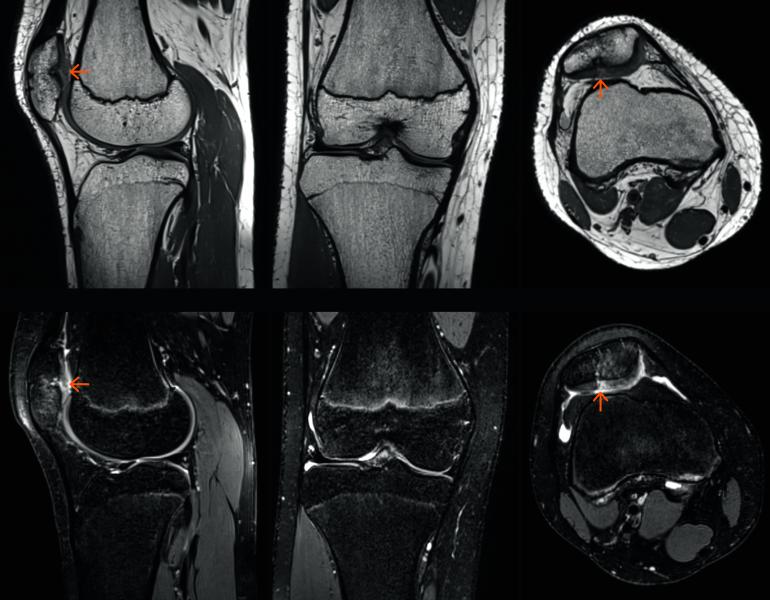

Magnetic resonance imaging (MRI) scans take too long. Siemens’ GOKnee3D, which is pending U.S. Food and Drug Administration (FDA) clearance, promises to cut the time for knee scans in half. Using the new Siemens technology, MR knee scans might be done in 10 minutes at 3T and 11 minutes at 1.5T.

Siemens prioritized the development of these technologies partly on the basis of procedure volume. Knee exams comprise the third most common MR scan (after brain and spine), accounting for about 11 percent of the 6.73 million done on Siemens MR systems, according to a 2016 company survey. Siemens engineers did not develop an accelerator package for spine MR, which represents the second most common MR scan, because of technical challenges, according to Daniel Fischer, Siemens head of clinical marketing for MRI. But the company has not given up.